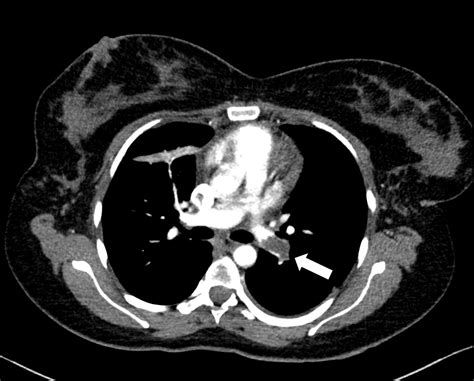

• Suspected pulmonary embolism

The radiation dose from a CT scan can vary significantly depending on the type of scan and the area of the body being imaged. The following table provides an approximate range of radiation doses for different types of CT scans:

Type of CT Scan Approximate Radiation Dose (mGy)

Head 1-2

Chest 7-8

Abdomen/Pelvis 10-20

Full Body 30-40

It’s important to note that the risk to the fetus depends not only on the radiation dose but also on the stage of pregnancy. The first trimester is the most critical period, as this is when organogenesis occurs. The risks decrease as the pregnancy progresses.